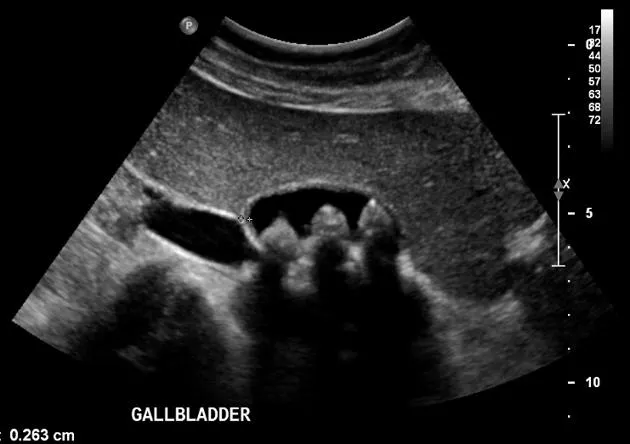

- Cholelithiasis: Mobile hyperechoic foci + posterior acoustic shadowing.

- Chronic Cholecystitis: Thick wall, WES sign (Wall-Echo-Shadow).

- Gallstones: hyperechoic foci with posterior acoustic shadowing; cholecystitis: wall thickening >3mm, sonographic Murphy's.